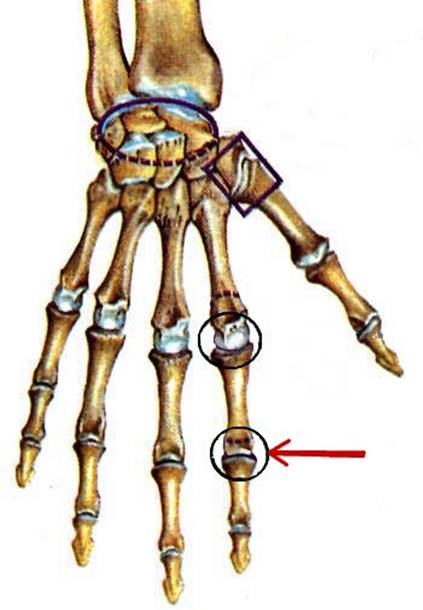

S: Числом 10 обозначена os trapezium (латинский язык).

S: Цифра 5 обозначает ossa metacarpi (латинский язык).

S: Цифрой 8 обозначена os capitatum

S: Числом 12 обозначена os scaphoideum

S: Числом 13 обозначена os triquetrum

S: Цифра 3 указывает на phalanx proximalis

S: Цифра 2 указывает на phalanx media

S: Цифра 1 указывает на phalanx distalis

S: Стрелка указывает на art. Radioulnaris distalis

S: Стрелка указывает на art. Radiocarpalis

S: Стрелка указывает на art. Mediocarpalis

S: Стрелка указывает на art. Carpometacarpalis

S: Стрелка указывает на art. Metacarpophalangea

S: Стрелка указывает на art. Interphalangea manus